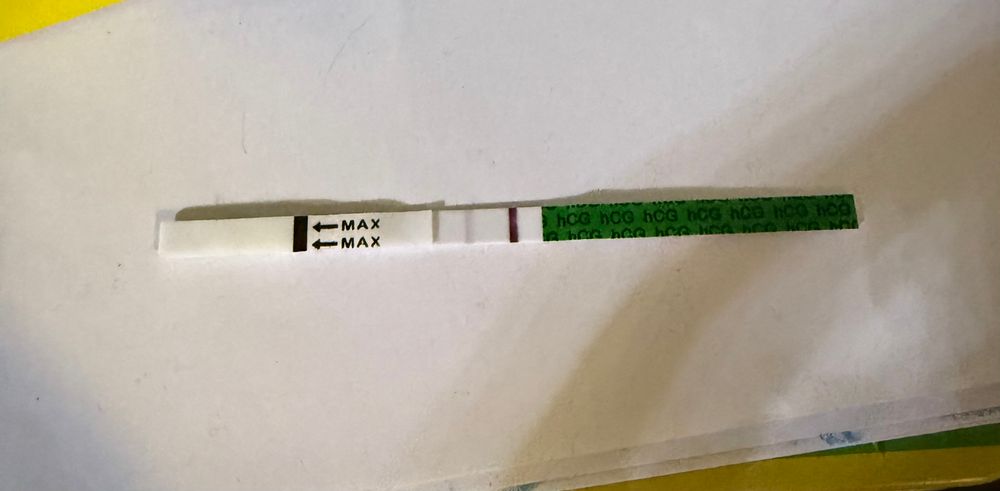

Танюня, о👀 у меня завтра должны быть и такой тест зеленый вчера тоже был точно такой же по яркости) попробую завтра сделать его посмотрю может в день задержки сравняется …. А то я на другие перешла там полоски почти сравнялись)

За день до такой полоски хгч был 526. Через 5 часов переделала, полоски сравнялись. Вроде, 15дпо был. У меня в дневнике есть фотки, тест такой же.